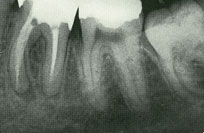

Radiografia com o 3° molar (ciso) semi-incluso (à direita)